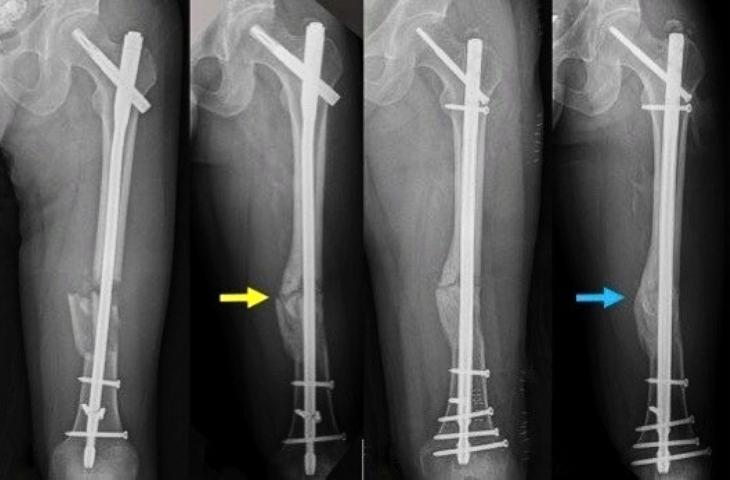

Phẫu thuật kết hợp xương sinh học bằng đinh nội tủy

Phẫu thuật kết hợp xương sinh học bằng đinh nội tủy thường được chỉ định cho bệnh nhân gãy từ 1/3 thân xương chi dưới, đặc biệt là các xương ống dài như xương đùi, xương chày... vì đinh nội tủy có khả năng chịu lực tỳ lớn trong khi chi dưới phải gánh trọng lực lớn khi cơ thể vận động, đi lại.

phẫu thuật kết hợp xương sinh học Phẫu thuật kết hợp xương sinh học sửu dụng đinh luồn vào trong ống tủy.

Kết hợp với bàn mổ chỉnh hình, màn tăng sáng C-arm, bác sĩ chỉ cần rạch da khoảng 3-4 cm để luồn đinh vào ống tủy rồi chốt ở hai đầu. Thủ thuật này giữ đinh và xương được nằm đúng vị trí trong quá trình liền xương, cố định vững chắc và ổn định toàn bộ chiều dài xương. Nhờ thế, hạn chế tối đa tổn thương phần mềm, bệnh nhân ít bị mất máu, ít đau, giảm nguy cơ nhiễm trùng và nhanh liền xương.